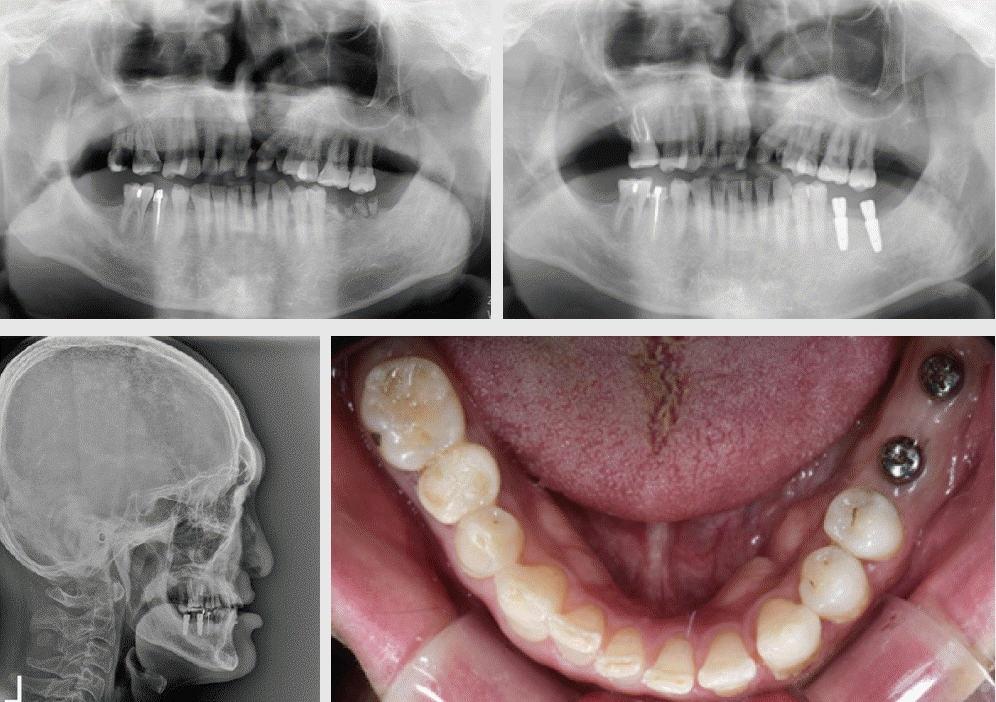

Figure 1.

Unilateral Cleft lip and Palate (Male, 36Y) and Bilateral Cleft Lip and Palate (Female, 20y)

- 구순구개열은 선천성 안면기형 중에서 발생 빈도가 가장 높은 질환으로 알려져 있다[1]. 아시아에서 비교적 높은 발생률이 보고되었고, 우리나라에서는 출생아 1,000 명당 1.8명이라고 보고된 이래[2], 홍과 백은 10년 간의 의료보험 청구자료를 분석하여 1.74명이라고 발표하였다[3], 출산율의 급격한 하락과 인구 절벽이라는 상황에서, 이환된 환자의 지속적이고 포괄적인 생애주기별 치료에 그 어느 때보다 높은 관심이 필요하다.전국민의료보험 치과 보장성 강화 대책의 일환으로, 2019년 3월 구순구개열 치과교정 급여화에 따른 급여기준이 시행된 이래, 2021년 10월 선천성 악안면 기형 질환 중 쇄골두개골이골증(Cleidocranial dysplasia), 두개안면골이골증(craniofacial dysostosis), 크루존병(Crouzon disease), 첨두유합지증(Apert syndrome)에 대하여 급여화의 확대 적용을 거쳐[1], 2022년 11월부터 선천성 악안면 기형 전체로 폭 넓게 적용하게 되었다. 그러나, 급여 대상자 선정 시의 혼란을 최소화하고자, 선천성 기형 환자의 경우에도 (극)희귀질환으로 등록된 자 또는 이력이 있는 자로 한정하였으며, 구순구개열을 동반하는 선천성 악안면 질환의 경우, 두 가지 중 하나만 등록하여도 급여 혜택을 받을 수 있게 되었다[1].내부 통계자료에 근거하여, 경북대학교 치과병원 치과 교정과에 2008년부터 2017년에 걸쳐 내원한 구순구개열 신규 환자는 연간 10명 내외였으나, 2019년의 급여화 이후 급여대상자로 등록된 신규 환자수는 연간 16.6명으로 증가하였다. 앞으로는 선천성 기형 환자들의 신규 내원도 증가할 것으로 예상된다.표준 의료 행위는 출생 이후부터 성장기를 거쳐, 성장완료 이후의 악교정 수술을 포괄하는 생애주기별 교정치료 내용들을 포함하고 있다. 따라서, ‘참1 술전유아악정형장치치료’로부터, ‘참6 고정식 교정장치를 이용한 교정치료’의 순서로 진행하는 것이 일반적이다[1]. 신환의 경우, 생후 3개월 경의 입술 봉합과 1~2세에 행하여지는 구개열 수술과, 전치의 배열, 악궁확장 그리고 견치 맹출 이전에 수행되어야 하는 이차 치조골 이식술(Secondary alveolar bone graft)의 이력을 확인하게 된다. 일반적인 2차 골이식술, 즉 치조열의 골이식 시기는 6~10세로 영구견치의 치근 1/2~2/3 형성 시기를 놓치지 않는 것이 중요하며, 측절치의 맹출을 고려하는 조기 2차 골이식술을 고려할 수도 있다고 알려져 있다[4].그러나, 환자의 첫 교정과 내원 시점에서, 치조골이식술의 이상적인 골이식 시기를 이미 지난 경우이거나, 양측성 구순구개열의 경우에는 골이식을 받아야 하는 이환 부위가 커서, 적기에 이식을 받았다 하여도, 치조열을 회복시킬 충분한 골가교(Bone bridg)가 형성되어 있지 않는 경우도 적지 않다(Figure 1). 좌측은 편측성 구순구개열(Unilateral Cleft Lip and Palate) 환자로 교정치료 이력이 없으며, 치조골 이식술에 대한 설명은 들었으나, 실행한 적은 없는 성인 남자였고, 우측은 적기에 2차 치조골이식술을 받은 이력은 있으나, 치아의 결손 및 치조열이 잔존한 상태로 내원한 양측성 구순구개열(Bilateral Cleft Lip and Palate)의 성인 여성이었다.Hira 빅데이터개방포털(https://opendata.hira.or.kr/op/opc/olapDiagBhvInfoTab3.do)에 따르면, 2019년에서 2022년까지 고정식 교정장치를 부착으로 보험급여 청구된 환자의 33.9%가 20세 이상의 성인이었다. 고정식 교정장치 부착 환자 세 명의 한 명 이상은 성인이었다. 또한 상악 견치가 이미 맹출 된 15세 이상의 환자들에게도 동일한 문제가 발생할 수 있다고 가정하면, 1차 치조골 이식을 받지 못했거나, 추가로 필요한 환자들의 수는 적지 않을 것이다[5].Figure 1에서 보듯이, 구순구개열 환자의 치열에서는 치아 수, 형태 및 맹출 이상이 보고되어 왔다. Baek & Yang [6]은 결손치 56.8%, 과잉치 11,2%, 매복치 18.3%, 왜소치 15.8%의 발생빈도를 보고하였고, Lee & Son [7]은 결손치 26.5%, 과잉치 17.6%, 왜소치 67.6%를 보고하였고, 회전 치아는 64.7%에 달하였다. 따라서, 95% 이상의 구순구개열 환자들에게서 적어도 하나의 치아 기형(Dental anomaly)이 관찰되며, 결손치는 Class III 부정교합을 초래하는 데 기여할 수 있고, 악교정 수술을 계획할 때, 정중선의 일치나 상하악 악궁 조화 시에 치아치조의 불균형으로 인한 방해요소가 될 수 있다[8]. 더구나, 구순구개열 환자는 출생부터 악안면 성장이 진행되는 동안, 일반 교정환자들에 비해 잠재적으로 수복 가능성이 높고, Cleft(열)에 인접한 치아들은 변색되고 법랑질 형성부전이 된 작고 저광화된 경우가 종종 발생한다고 알려져 있다. 이러한 경우 교정용 브라켓 부착이 어려울 뿐 아니라 브라켓 제거 시 수복물에 손상이 생길 수도 있다[8].이러한 일반적인 특성을 더하여, 결정적으로 이차 치조골 이식의 최적 시기를 이미 지난 상태에서 여전히 치조열 부위에 골이식이 가능하도록 치아를 배열하는 것 그리고 여러 방향으로 수축되어 삼각형, 람다, 오메가의 형태를 보이는 상악궁의 형태를 하악궁과 대합이 가능하도록 조정하는 치료는 임상적 난제이다. 특히 오메가 형태의 악궁은, 전치부, 소구치부, 구치부 등 악궁의 부분마다 횡적인 부조화의 양과 방향이 일관되지 않아 단계적인 접근을 수행하여야 한다.따라서, 본 증례 보고는 두 가지 구순구개열 증례, 즉 편측성 및 양측성 구순구개열 (UCLP & BCLP)에서 상악궁의 형태를 재형성하면서, 치조골 이식을 수행한 과정을 소개하고자 한다.

Figure 2.

Patient’s chief complaints at lower left molars and Dental implants at the referral to the orthodontic department.